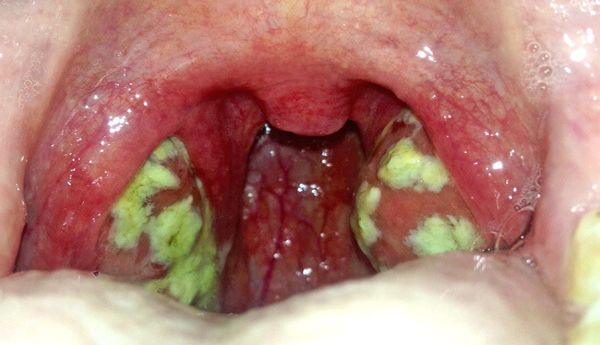

Небные миндалины увеличены, отечны. На миндалинах видны нагноившиеся фолликулы в виде бело-желтых образований величиной с булавочную головку (картина «звездного неба»). Нагноившиеся фолликулы вскрываются, образуя гнойный налет, не распространяющийся за пределы миндалин.

Лакунарная ангина.

Налет за пределы миндалин не выходит.

Длительность течения лакунарной ангины — 5-9 дней. Проявления ее нарастают быстро и также быстро стихают. В период исчезновения проявлений начинается очищение миндалин от налетов.

Увеличение близрасположенных лимфатических узлов держится дольше — до 10—12 дней. Характерно выраженное покраснение миндалин, их отек; желтовато-белое содержимое лакун образует на поверхности миндалин рыхлый налет в виде мелких очагов или пленки. Налет не выходит за пределы миндалин, он тусклый, рыхлый, легко удаляется, не оставляя кровоточащего дефекта.